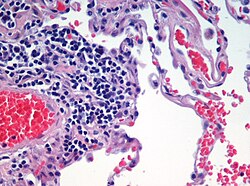

Microscopic view of a histologic specimen of human lung, consisting of various tissues: blood, connective tissue, vascular endothelium and respiratory epithelium, stained with hematoxylin and eosin.